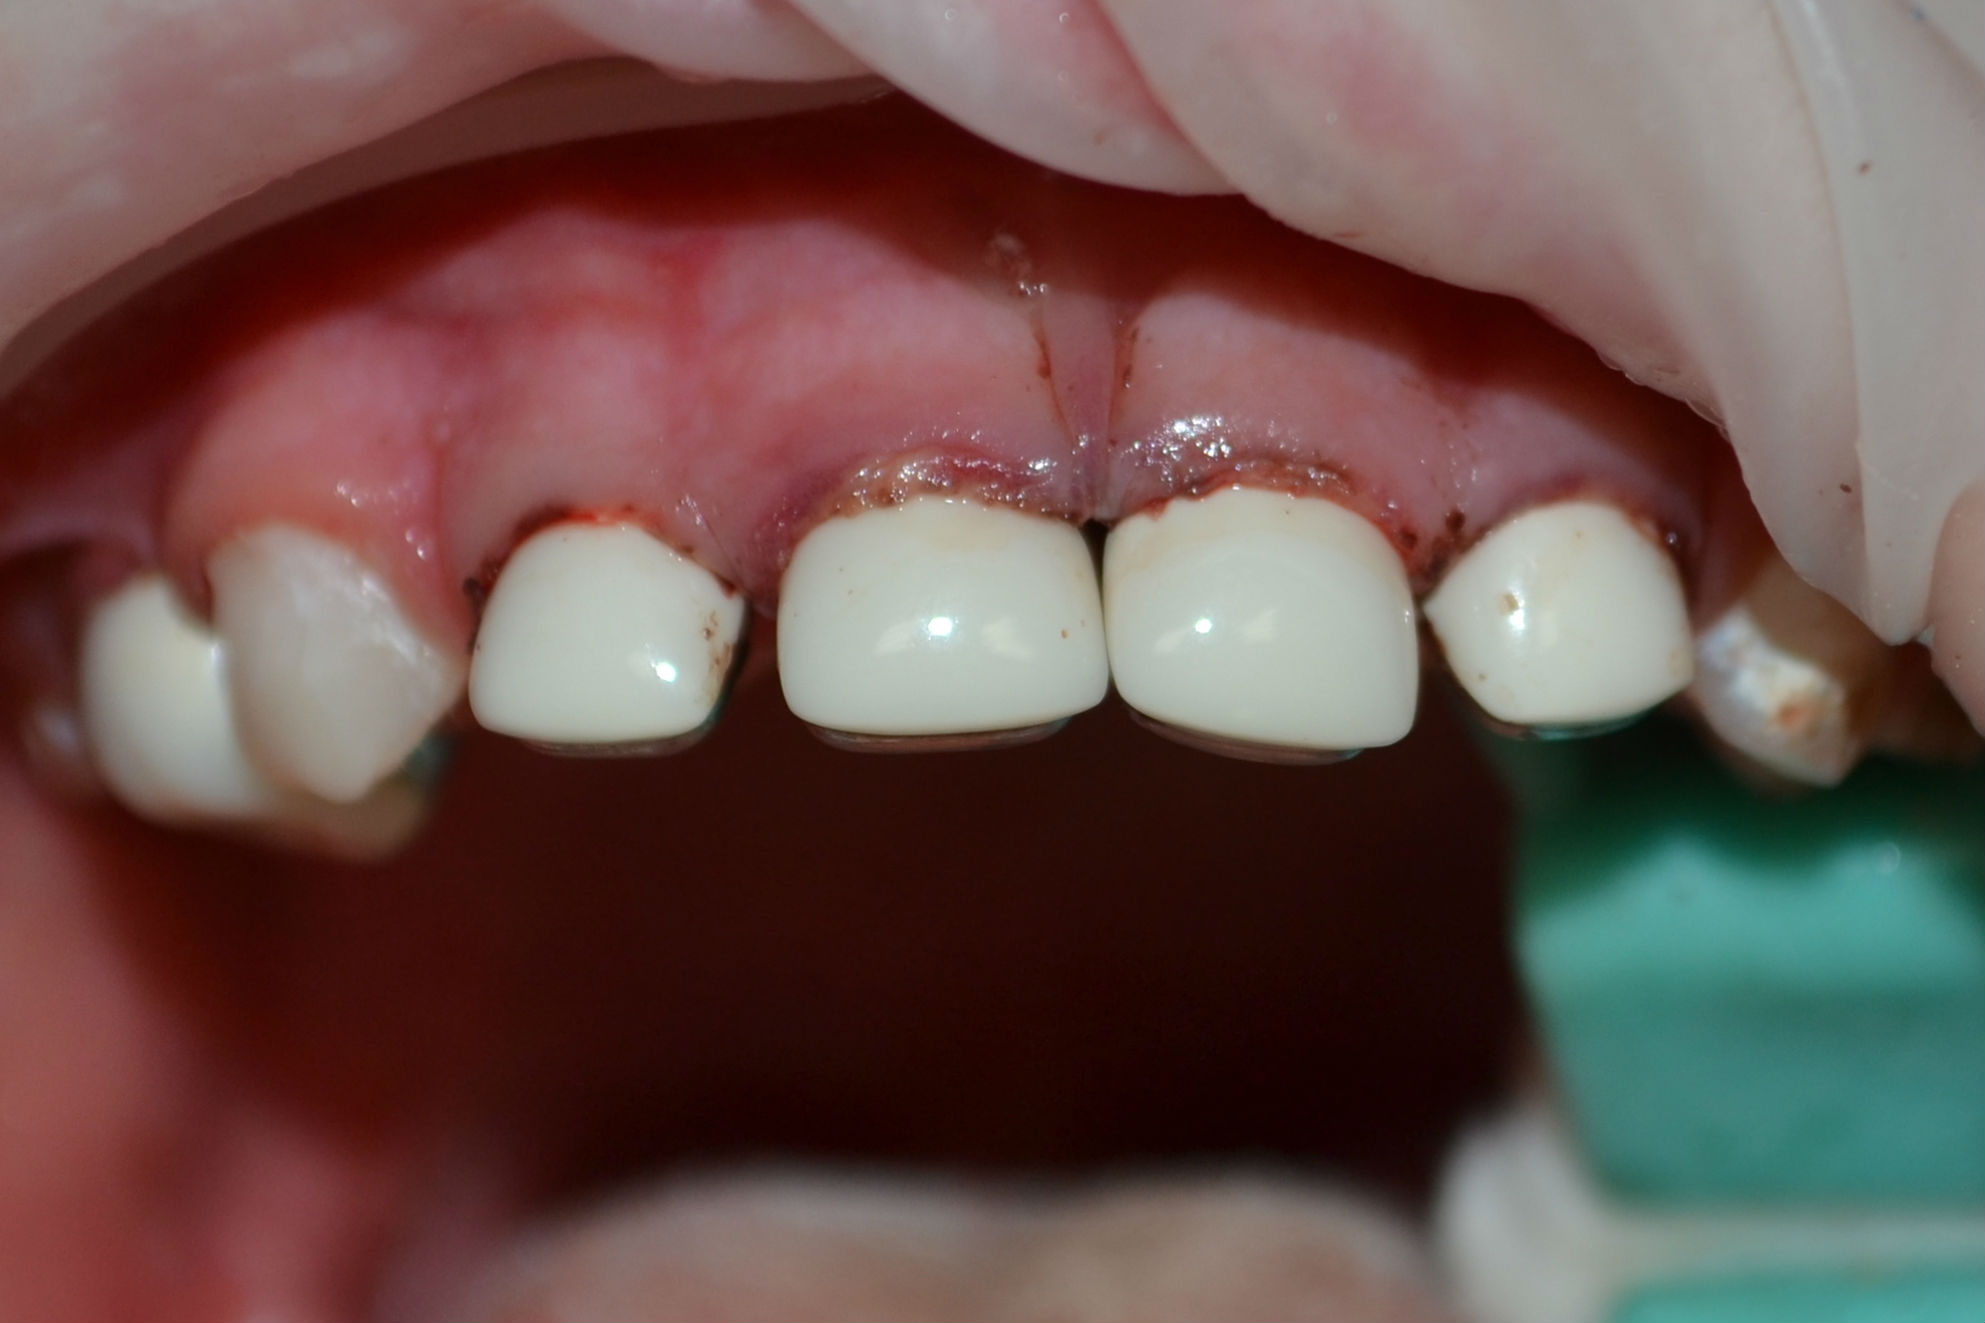

Показания и противопоказания

Основными ситуациями, когда врачи настаивают на установке коронки вместо пломбирования или других способов лечения, являются следующие:

- разрушение твердых тканей от кариеса произошло уже более, чем на половину объема;

- наблюдаются проблемы, влияющие на правильное развитие эмали;

- при механических повреждениях и травмах (переломах, сколах и пр.);

- повышенная активность болезнетворных бактерий, которые приводят к быстрому распространению кариеса в ротовой полости;

- после депульпирования;

- в случаях косметических дефектов, особенно во фронтальной части ряда;

- как средство борьбы с кариесом в начальной стадии;

- при бруксизме, во избежание стираемости естественных тканей;

- флюороз и покрытие эмали пятнами.

Особенностью установки коронок на молочные зубы является то, что практически не надо обтачивать здоровые ткани, что значительно упрощает процедуру и не вызывает страха у детей. Но есть и противопоказания, которые следует учитывать. Коронки нельзя поставить в тех случаях, когда у ребенка наблюдается аллергическая реакция на металлы, используемые при их создании.